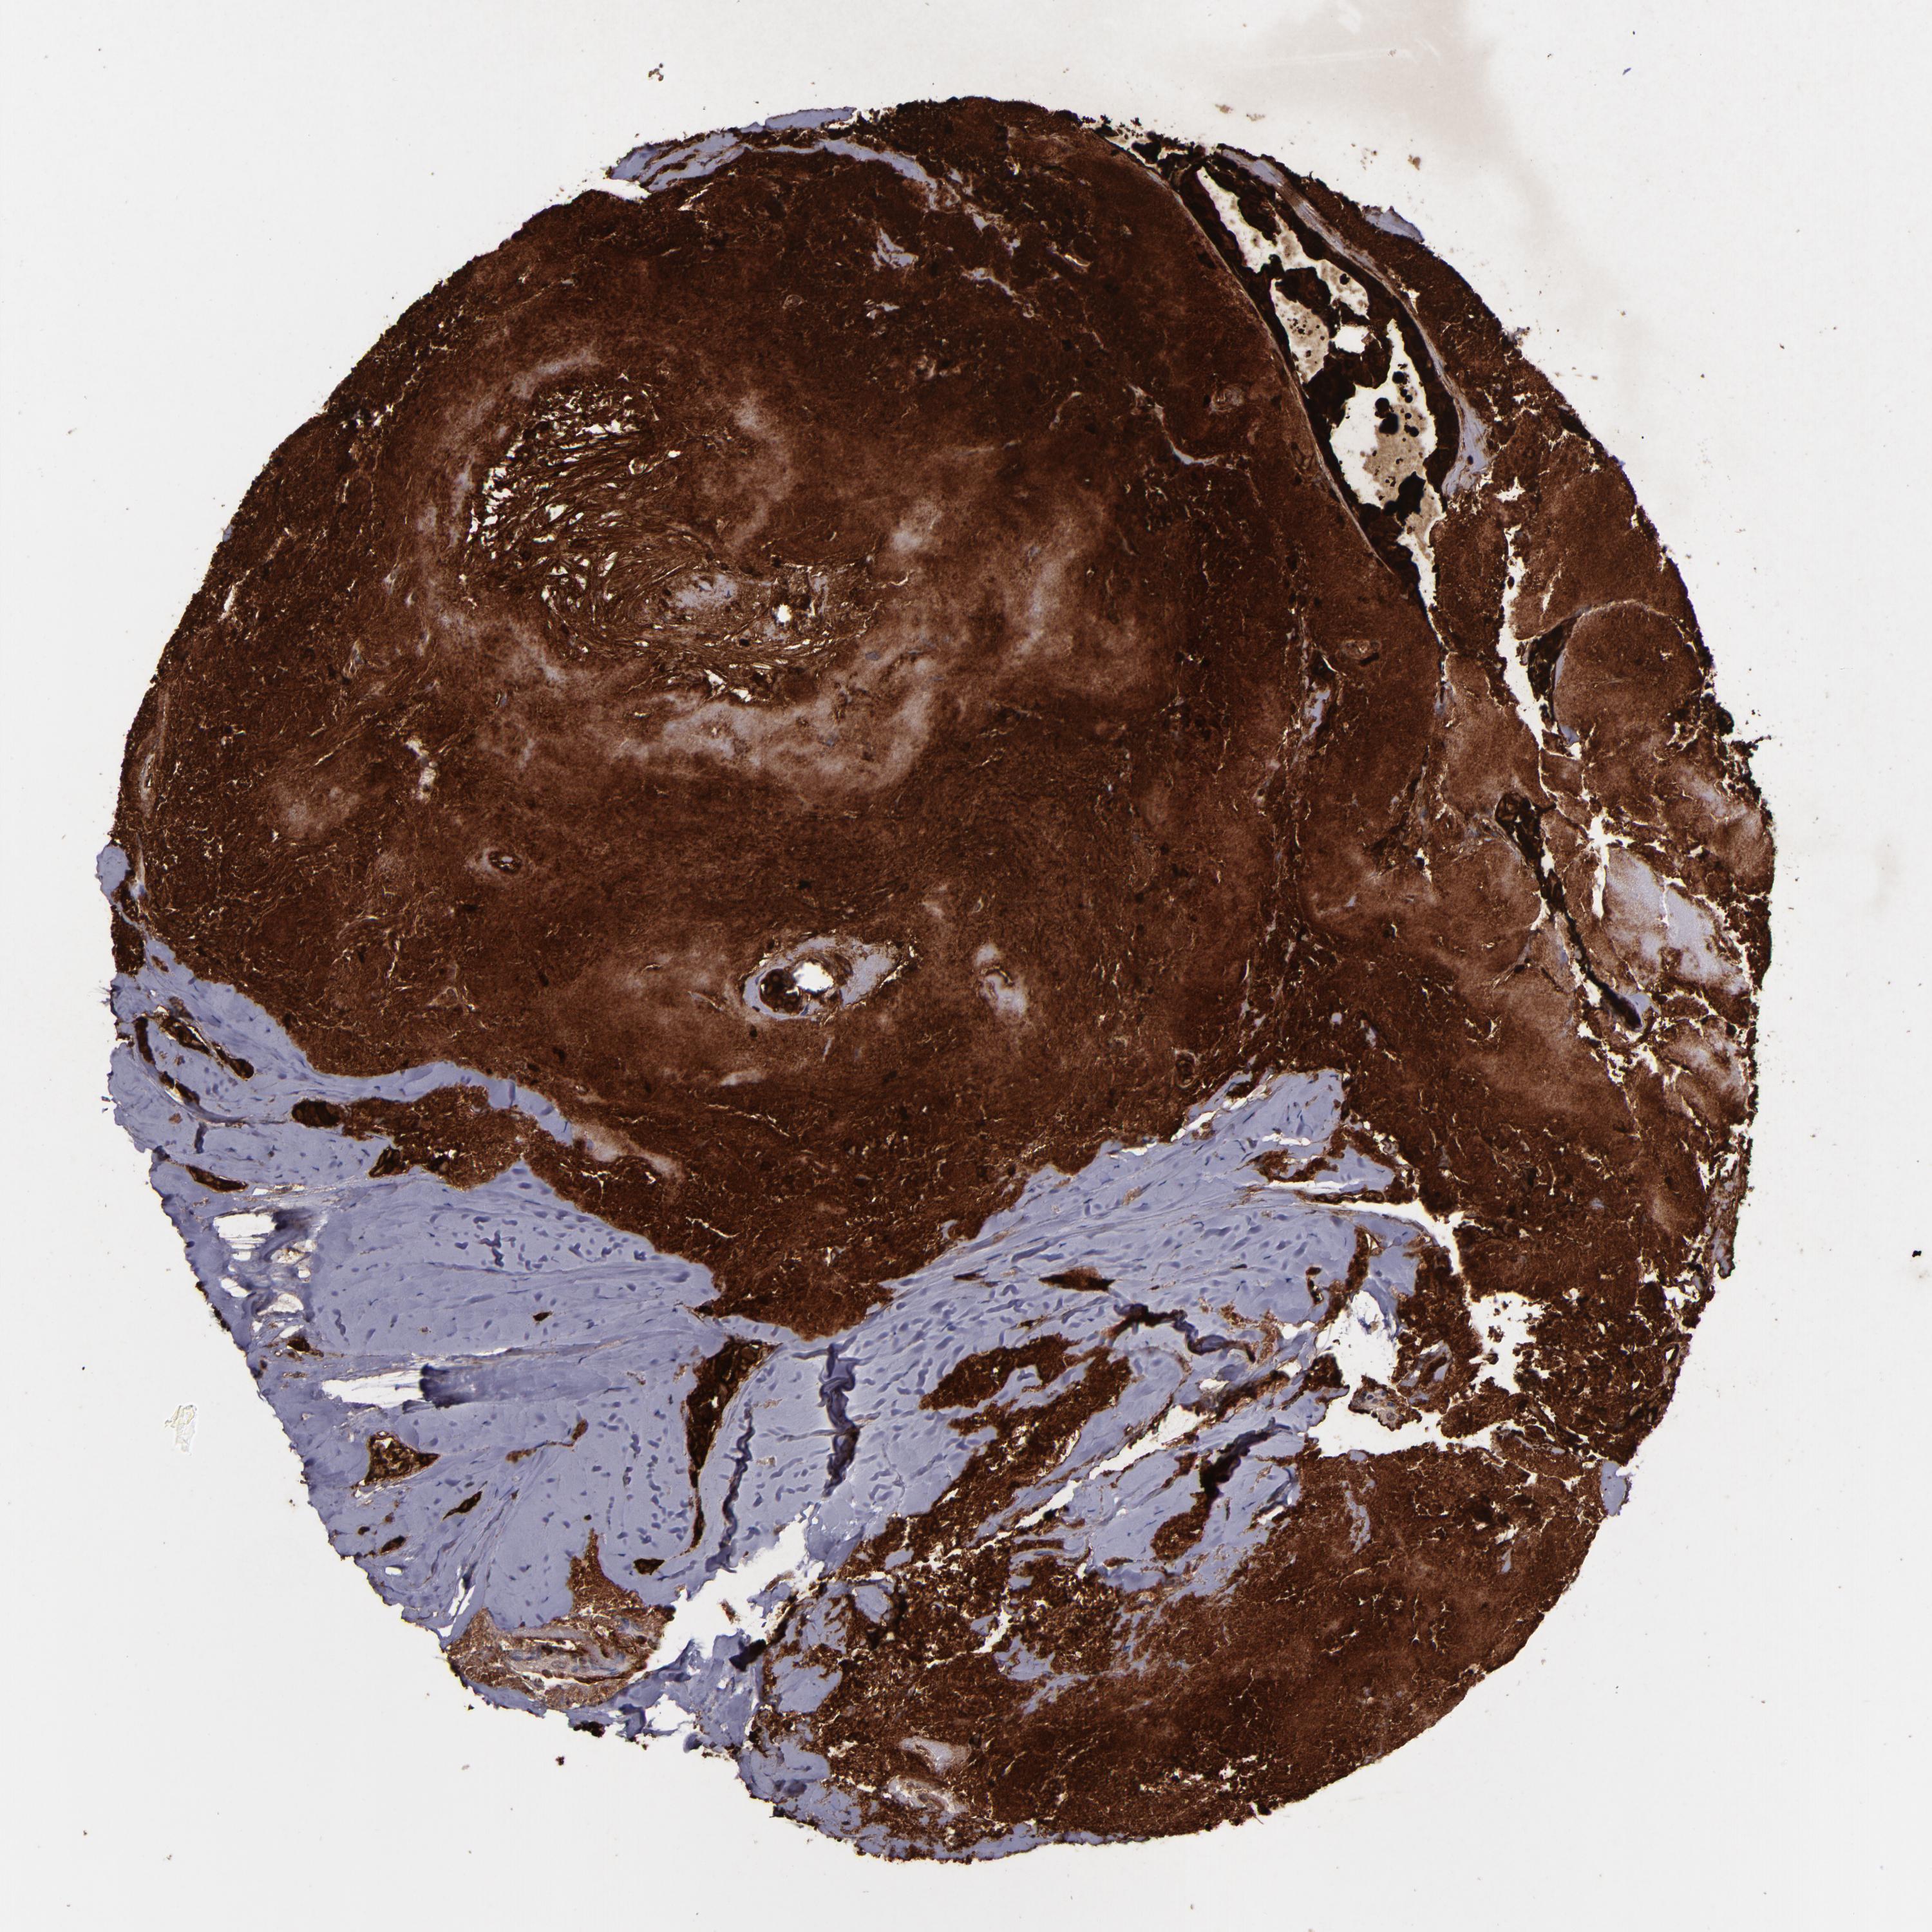

CANCER BREAST CANCER Show tissue menu

BRCA TCGA BRCA VALIDATION PROTEIN EXPRESSION